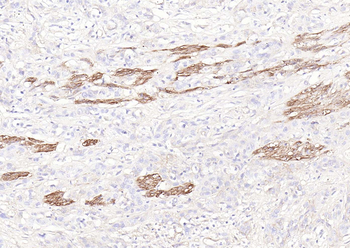

IHC staining of FFPE human pancreatic carcinoma with CD73 antibody (clone NT5E/2545). HIER: boil tissue sections in pH9 10mM Tris with 1mM EDTA for 10-20 min and allow to cool before testing.